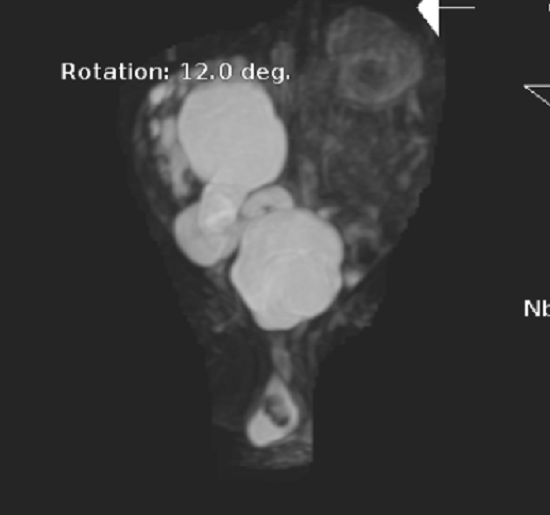

然而,在乐乐刚满月时,情况骤然急转。突然出现高热、腹胀,病情进展迅猛,入住该院新生儿监护室(NICU)。经紧急检查,确诊为右侧重复肾输尿管畸形合并输尿管黏膜膨出,继发脓肾可能。此时,大量脓液积聚在重复肾的集合系统中,不仅导致肾脏功能急剧受损,更随时可能引发脓毒血症、感染性休克等危及生命的全身性感染。

时间就是生命。小儿泌尿外科团队迅速启动应急预案,在完善术前准备后,为乐乐实施了右侧输尿管皮肤造口术。手术中,医生通过一个微小的造口,将一根双J管置入积脓的输尿管,当即引流出大量脓性尿液。术后,乐乐的发热、腹胀症状迅速缓解,感染指标明显下降,病情转危为安。